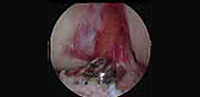

Reparación artroscópica acromio-clavicular de hombro

Incorporamos la reparación de las luxaciones acromio-claviculares de hombro con técnica artroscopica y minimas incisiones. Se trata de un avance importante que permite un mejor tratamiento de estas complejas lesiones, con mínimas incisiones y por tanto evitando las importantes cicatrices que se producen con la técnica habitual de cirugía. Tras 2 años de experiencia los resultados en más de 25 pacientes son alentadores.

Reparación artroscópica de las fracturas de 1/3 distal clavícula

Introducimos esta nueva técnica de reparación por cirugía artroscópica de las fracturas desplazadas del 1/3 distal de clavícula con mínimas incisiones y resultados preliminares satisfactorios. Disminuimos de manera notable las cicatrices a nivel del hombro que provoca la cirugia convencional y conseguimos un mayor confort postoperatorio para los pacientes.